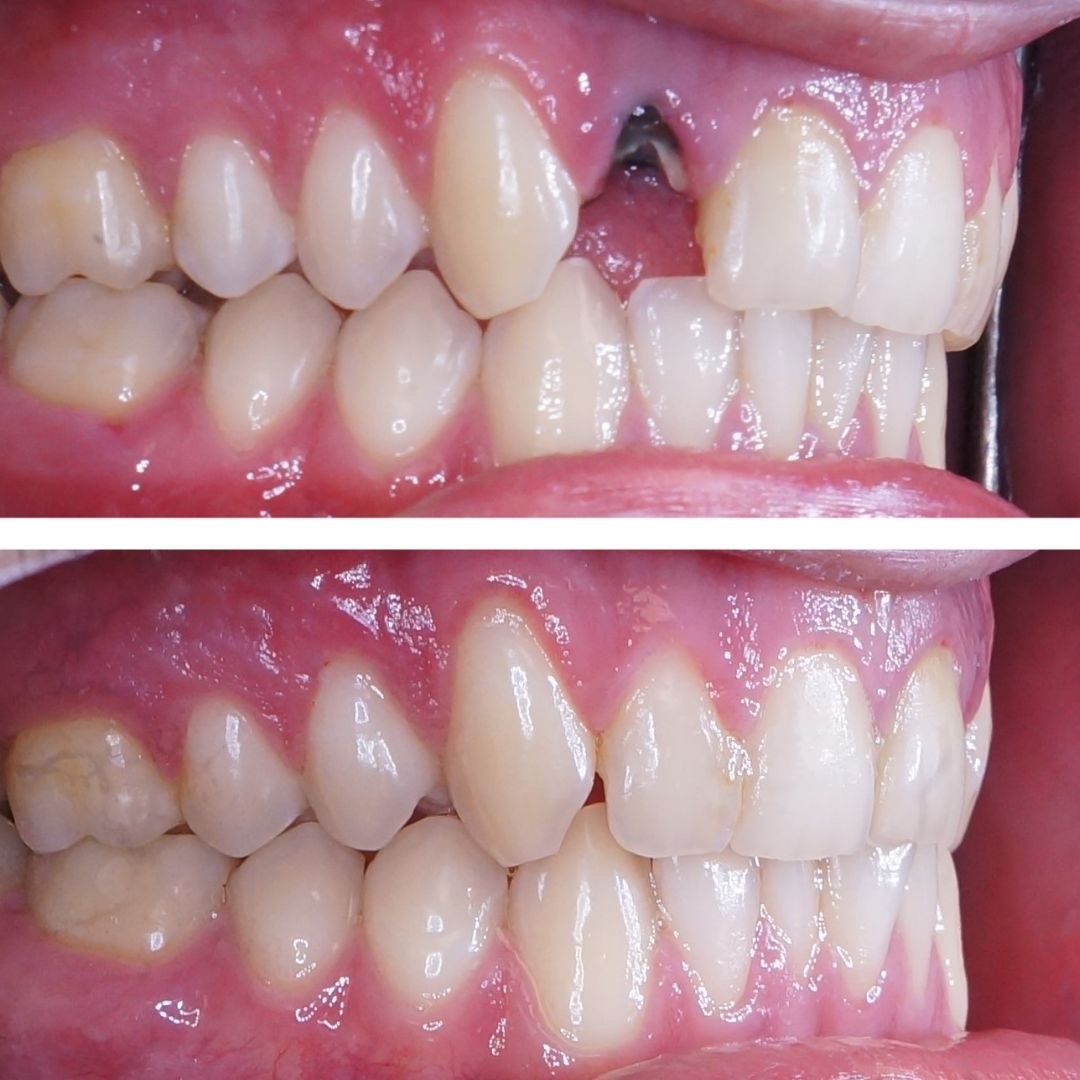

Стоматология «5 Принципов» в Симферополе гордится своими достижениями в области имплантации и постоянного совершенствования качества обслуживания. Наши клиенты получают индивидуально подобранные решения, основанные на передовых технологиях, годах опыта и внимании к деталям. Мы предлагаем комплексный подход: от подробной консультации до восстановления жевательной функции и эстетики улыбки.Каждый этап начинается с точной диагностики: цифровая томография, планирование в 3D, моделирование улыбки. Это позволяет увидеть предполагаемые результаты до начала операции и минимизировать риски.

При имплантации мы используем современные системы имплантатов с высоким процентом приживления и минимальным временем восстановления. Наши специалисты владеют техниками одномоментной фиксации и протезирования без необходимости временной съемной конструкции, что обеспечивает быструю адаптацию и комфорт пациента.В портфолио клиники — примеры успешных восстановлений: имплантация одиночного зуба с естественным оттенком коронки, комплексная реконструкция зубного ряда, а также имплантация с последующим использованием циркониевой коронки для максимальной эстетики. Мы уделяем внимание функциональности, долговечности и гармонии с природной линией улыбки.Послеоперационное сопровождение — важная часть our подхода: контроль за имплантатами, профилактические процедуры и рекомендации по уходу. В «5 Принципы» мы стремимся вернуть уверенность и комфорт улыбке каждого клиента в Симферополе.